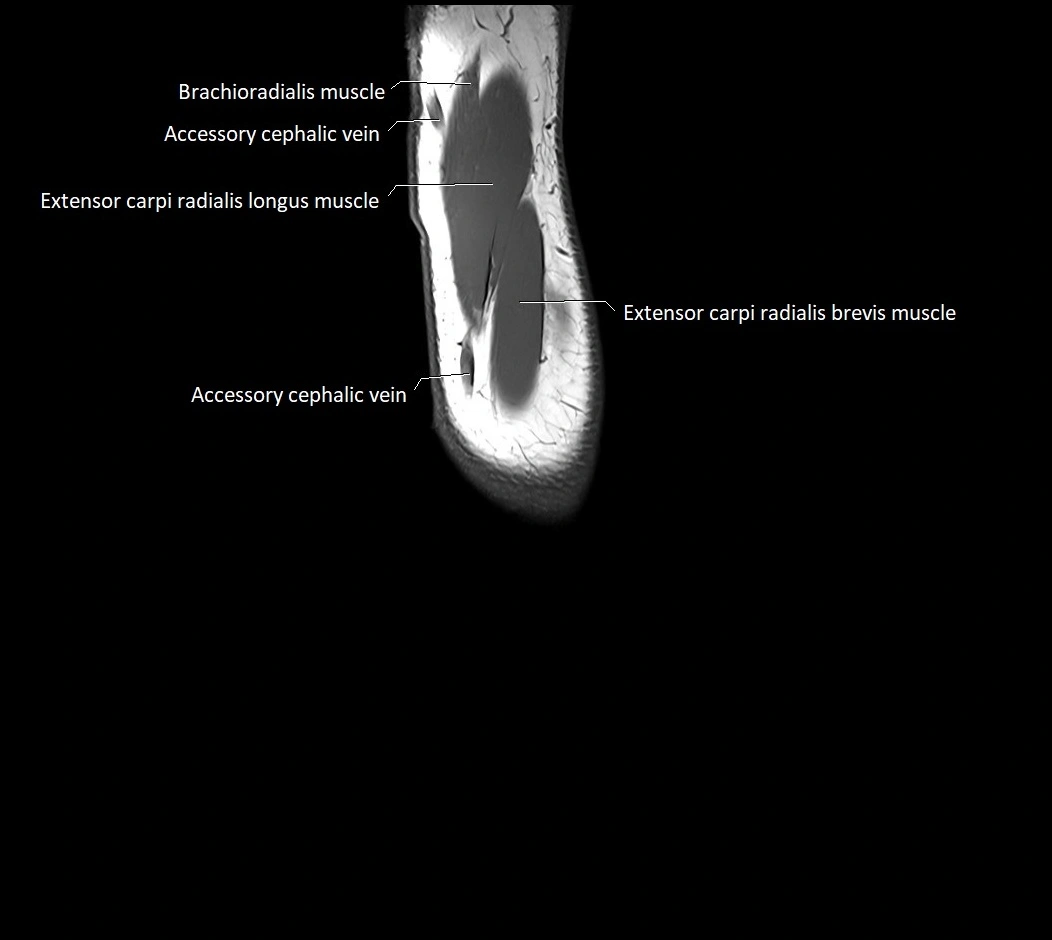

MRI images

image